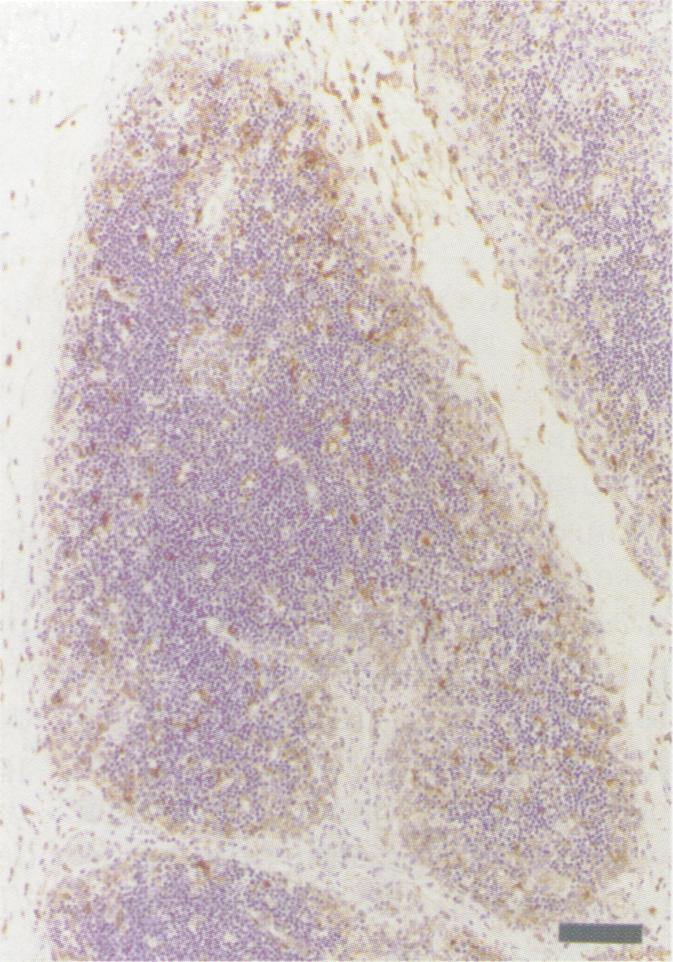

During the past several years, acute infections with bovine viral diarrhea virus (BVDV) have been causally linked to hemorrhagic and acute mucosal disease-like syndromes with high mortality. The majority of BVDVs isolated in such cases have been classified as type II on the basis of genetic and antigenic characteristics. It was our objective to examine clinical disease, lesions and potential sites of viral replication, following experimental BVDV type II infection in young calves. On approximately day 35 after birth, calves that had received BVDV-antibody-negative colostrum were infected by intranasal inoculation of 5 x 10(5) TCID50 of BVDV type II isolate 24,515 in 5 mL of tissue culture fluid (2.5 mL/nostril). Calves were monitored twice daily for signs of clinical disease. Approximately 48-72 h after infection, all calves developed transient pyrexia (39.4-40.5 degrees C) and leukopenia. Beginning on approximately day 7 after infection, all calves developed watery diarrhea, pyrexia (40.5-41.6 degrees C), marked leukopenia (> or = 75% drop from preinoculation values), variable thrombocytopenia, and moderate to severe depression. Calves were euthanized on days 10, 11, or 12 after infection due to severe disease. Gross and histological lesions consisted of multifocal bronchointerstitial pneumonia (involving 10%-25% of affected lungs), bone marrow hypoplasia and necrosis, and minimal erosive lesions in the alimentary tract. Immunohistochemical staining for BVDV revealed widespread viral antigen usually within epithelial cells, smooth muscle cells and mononuclear phagocytes in multiple organs, including lung, Peyer's patches, gastric mucosa, thymus, adrenal gland, spleen, lymph nodes, bone marrow, and skin. This BVDV type II isolate caused rapidly progressive, severe multisystemic disease in seronegative calves that was associated with widespread distribution of viral antigen and few gross or histological inflammatory lesions.

在过去几年中,牛病毒性腹泻病毒(BVDV)急性感染与高死亡率的出血性及急性黏膜病样综合征存在因果关联。在此类病例中分离出的大多数BVDV,根据遗传和抗原特性被归类为II型。我们的目的是在幼龄犊牛经实验性感染II型BVDV后,检查其临床疾病、病变以及病毒复制的潜在部位。出生后约35天,接受了BVDV抗体阴性初乳的犊牛通过鼻内接种5 mL组织培养液(每侧鼻孔2.5 mL)中的5×10⁵ TCID₅₀ II型BVDV分离株24,515进行感染。每天对犊牛监测两次临床疾病体征。感染后约48 - 72小时,所有犊牛出现短暂发热(39.4 - 40.5摄氏度)和白细胞减少。从感染后约第7天开始,所有犊牛出现水样腹泻、发热(40.5 - 41.6摄氏度)、显著白细胞减少(较接种前值下降≥75%)、可变的血小板减少以及中度至重度抑郁。由于严重疾病,犊牛在感染后第10、11或12天实施安乐死。大体和组织学病变包括多灶性支气管间质性肺炎(累及10% - 25%的患肺)、骨髓发育不全和坏死,以及消化道的轻微糜烂性病变。对BVDV进行免疫组织化学染色显示,病毒抗原广泛存在于多个器官的上皮细胞、平滑肌细胞和单核吞噬细胞内,包括肺、派伊尔氏淋巴集结、胃黏膜、胸腺、肾上腺、脾脏、淋巴结、骨髓和皮肤。这种II型BVDV分离株在血清阴性犊牛中引起迅速进展的严重多系统疾病,这与病毒抗原的广泛分布以及极少的大体或组织学炎症病变相关。